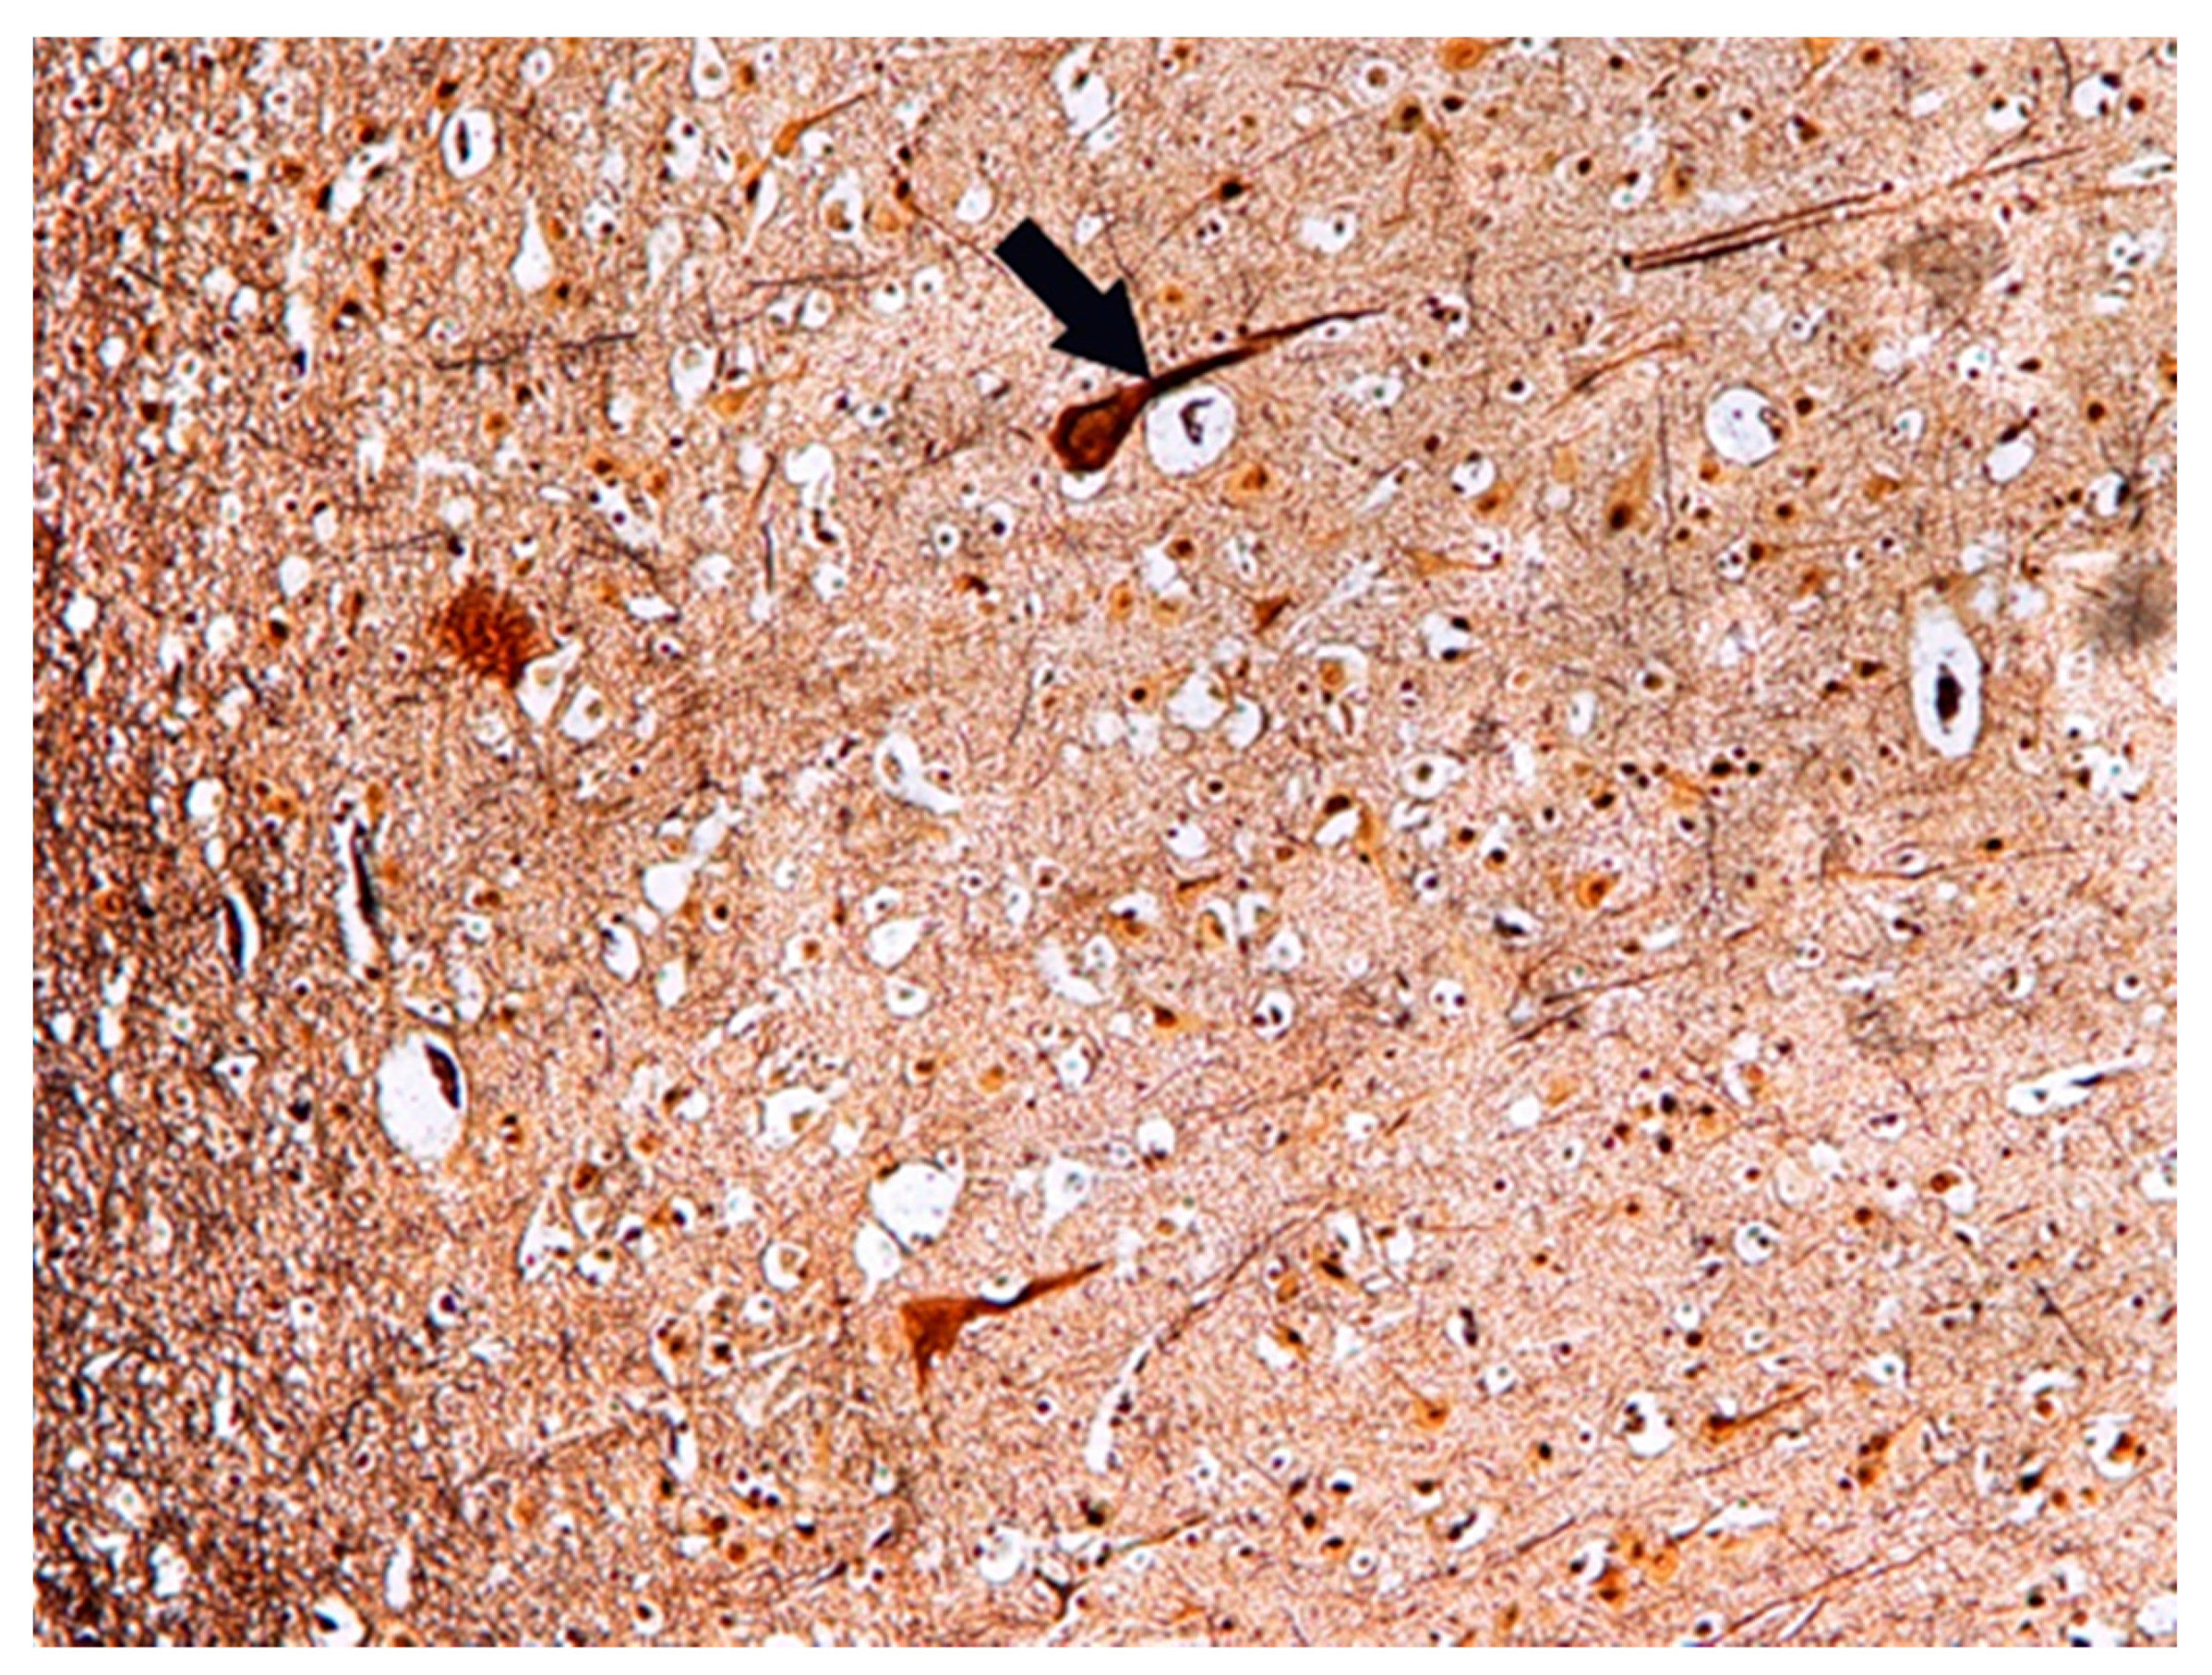

Histochemical Methods